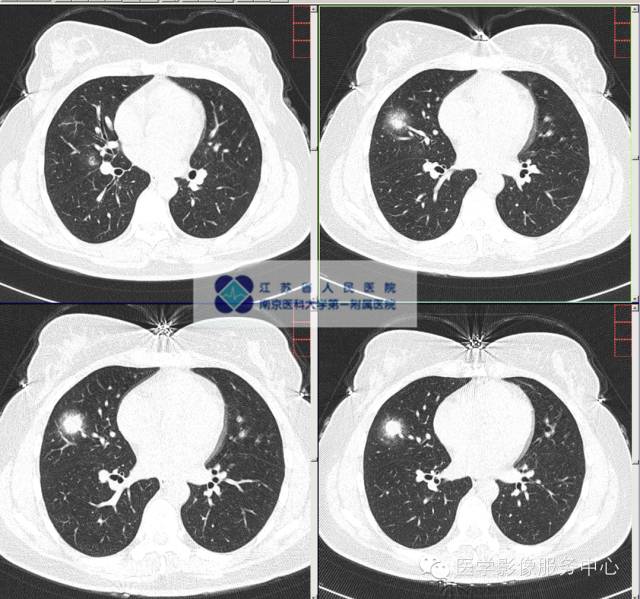

影像分析:右肺中叶多发病灶,较大病灶较2015-03-27片增大、变实,考虑为CA?感染?COP?建议穿刺活检明确病灶性质。

2、部分病灶可出现分叶征、毛刺征、胸膜凹陷征、血管集束征或厚壁不规则空洞等类肺癌征象,易与周围型肺癌相混淆,但上述征象的发生率均较低。

3、在空泡或空洞:多数空洞壁薄,内见分隔带,部分空洞内见附壁结节,典型者呈“空气新月征”,提示真菌感染。

5、增强后较多呈中等程度强化(CT净增值20~57 HU)和均匀强化,部分可出现液化坏死区。